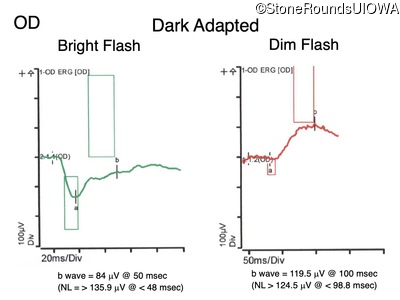

Congenital Stationary Synaptic Dysfunction (IA2g)

Congenital Stationary Synaptic Dysfunction (IA2g)

| Congenital Stationary Synaptic Dysfunction | CABP4 | Arg49Stop CGA>TGA | IVS1+1 G>T | AR |